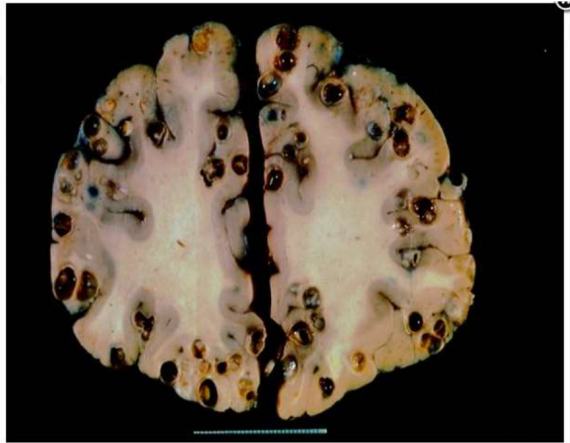

A Central American patient presents with new onset seizures. CT shows hydrocephalus, and muitiple calcified lesions. MRI

demonstrates rim-enhancing cysts throughout the brain. What is the most likely etiology?